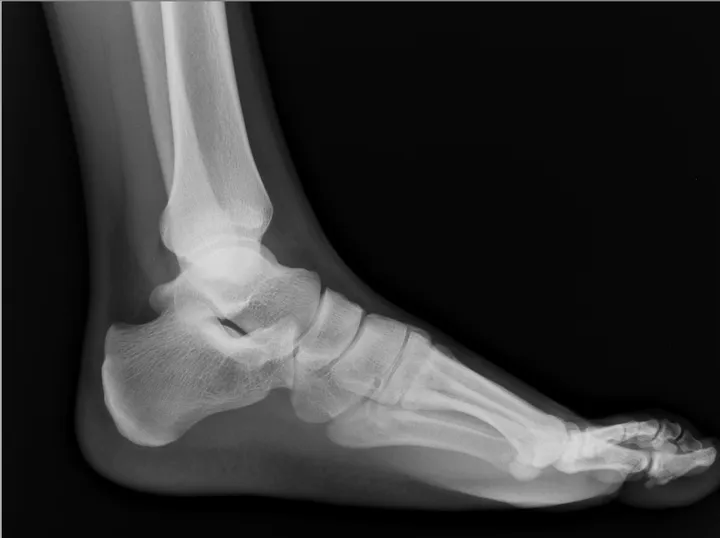

X-ray of foot You likely think of your bones as part of a system, connected to one another by joints. Sesamoids are exceptions to this rule, "free floating" bones that offer a smooth surface for your tendons to slide over, creating a sort of pulley system for the muscles. The sesamoids in your feet help you as you walk, and without them, your big toe would lose some of its power and force. Sesamoiditis itself is pain or inflammation of the sesamoids.